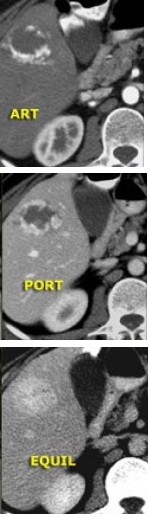

Diagnóstico: Hemangioma.